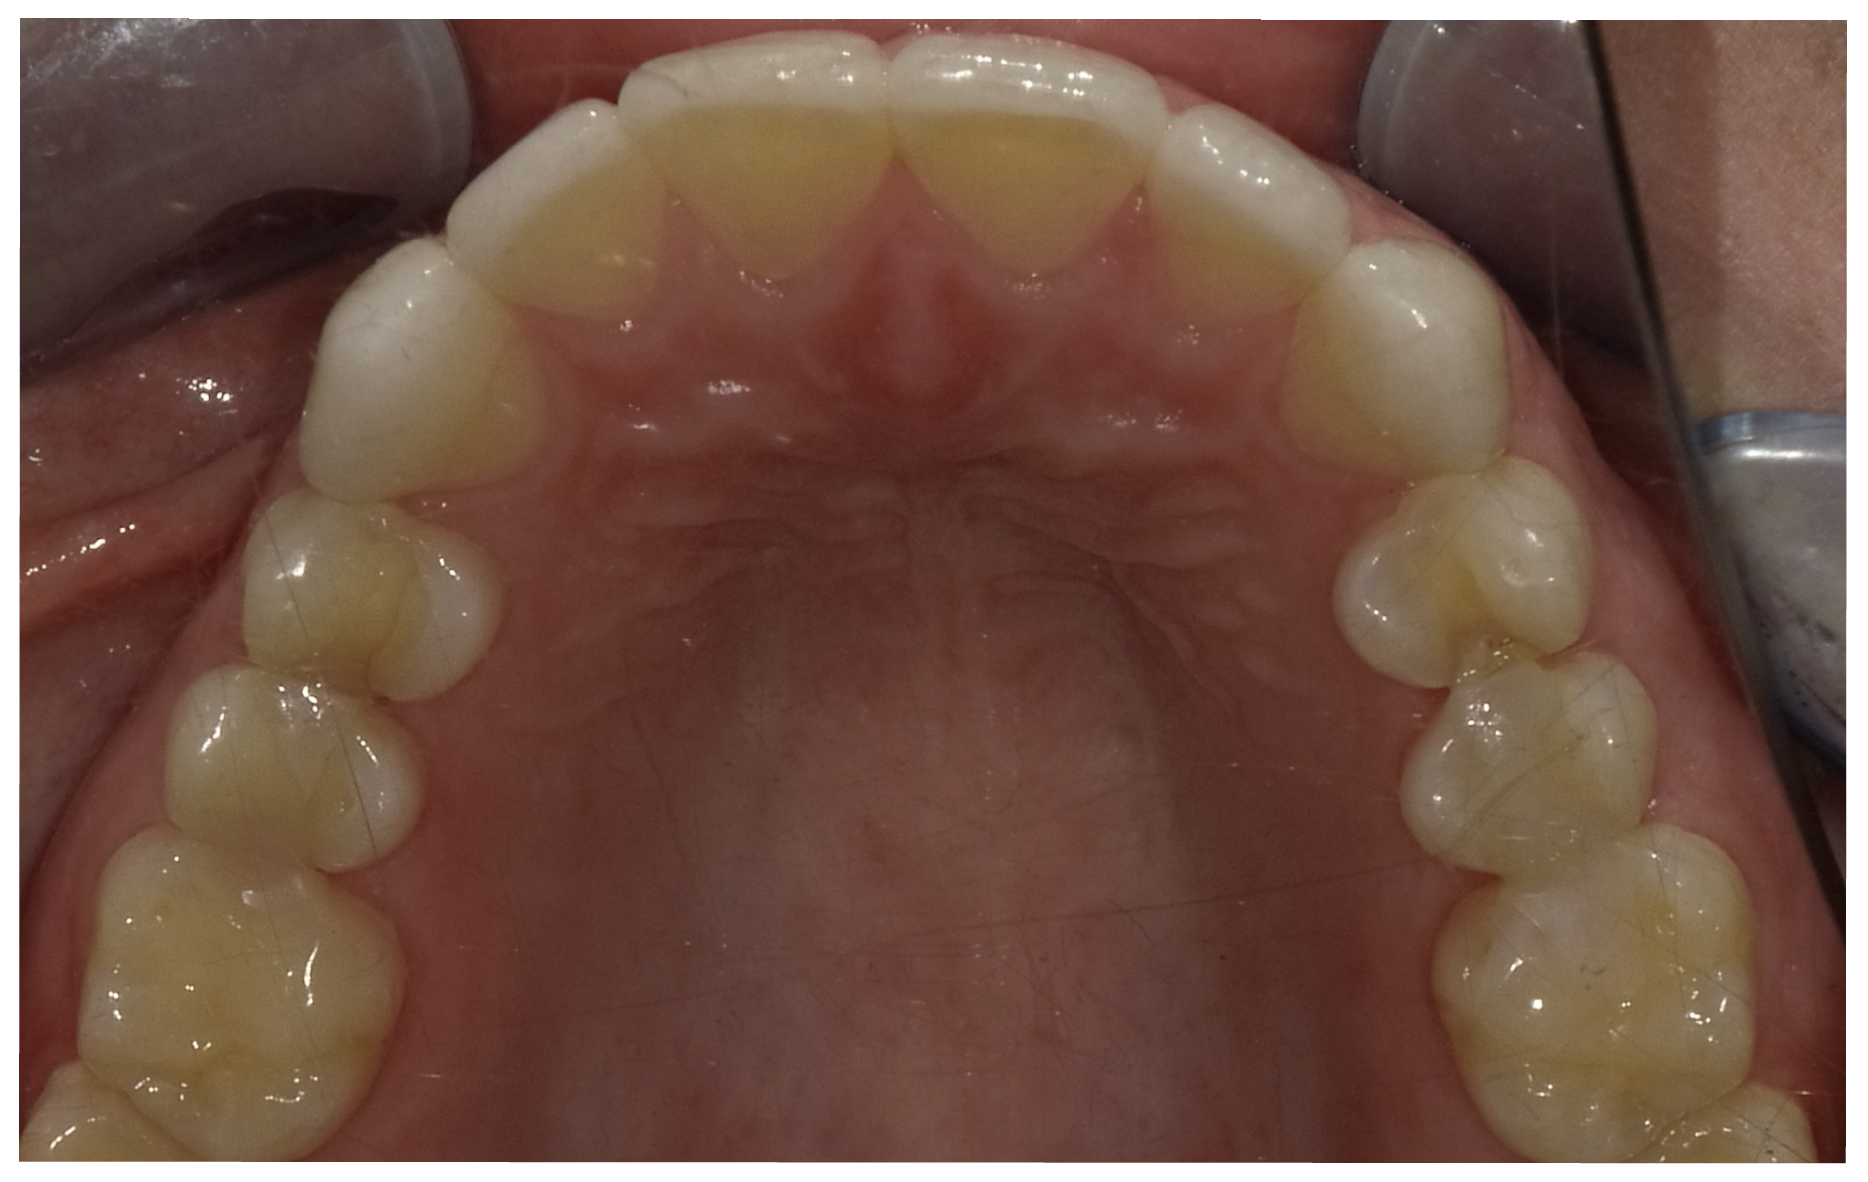

In another case, the patient presented with very thick, bulky, over-contoured veneers done on teeth Nos. 7 through 10 when she was a teenager. There also was some recession and staining at the margins (Figure 12). The clinician decided to restore teeth Nos. 6 through 11. A preparation design was required with provisionals removed. As tooth structure could not be regrown, the practitioner made the best of the situation. There was good gum health, which is important for isolation and marginal seal. The clinician cemented with a universal, doing six units at one time. Minimal cleanup was required. At a 1-month follow-up visit, although tissue still was settling in, the contours were natural. After a year (Figure 13), the gum filled in nicely and was in excellent health, and there was good color stability and seamless marginal integrity.